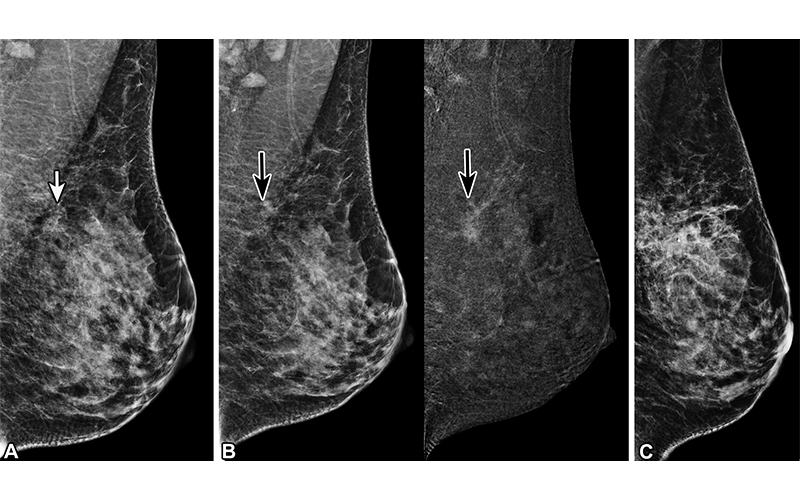

Complex sclerosing lesion (CSL) CSL in a 41-year-old woman. (A) Screening mediolateral oblique DBT mammogram of the left breast shows architectural distortion (arrow). The patient was recalled for contrast-enhanced mammography. (B) Mediolateral oblique contrast-enhanced mammogram (left) and recombined image (right) of the left breast shows nonmass enhancement (arrows, left) (C) Mediolateral digital mammogram shows the biopsy clip at the site of architectural distortion. DBT-guided core biopsy was performed, revealing CSL, which was confirmed at subsequent surgical excision. https://pubs.rsna.org/doi/10.1148/rg.230022 ©RSNA 2023